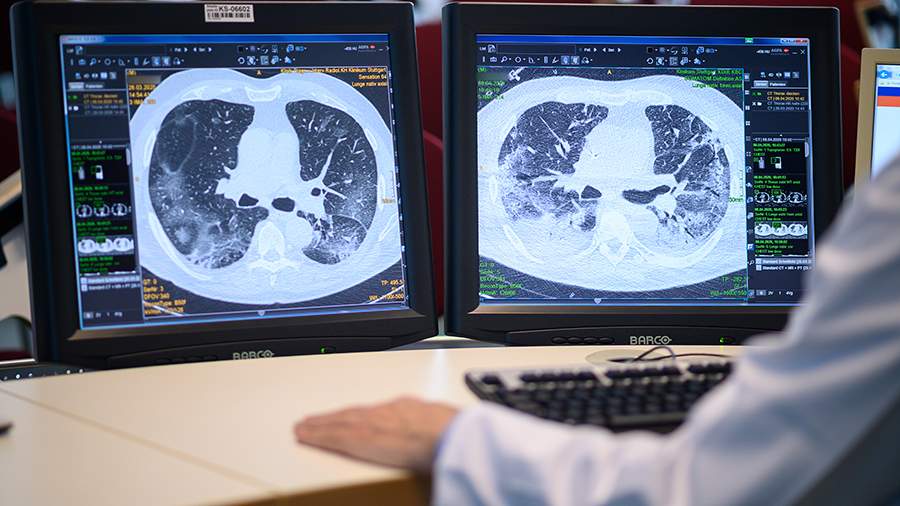

Фото: Global Look Press/dpa/Sebastian Gollnow

Приемная врача общей практики в английском Донкастере ошибочно разослала сотням пациентов сообщения о том, что у них якобы последняя стадия рака легких. Об этом 29 декабря сообщила газета The Times.

«Врач попросил заполнить (форму) DS1500 для вышеуказанного пациента. Диагноз — агрессивный рак легких с метастазами», — цитирует издание текст сообщения, который пациенты разместили в соцсетях.

DS1500 — это тип формы, которая позволяет неизлечимо больным людям претендовать на пособия.

Спустя 22 минуты пациенты получили сообщение с «искренними извинениями», где говорилось, что текст сообщения должен был звучать так: «Мы желаем вам очень счастливого Рождества и счастливого Нового года». Однако, по данным издания, это ситуацию не исправило: людей, которые на самом деле живут в ожидании своего диагноза, данный инцидент шокировал и довел до слез.